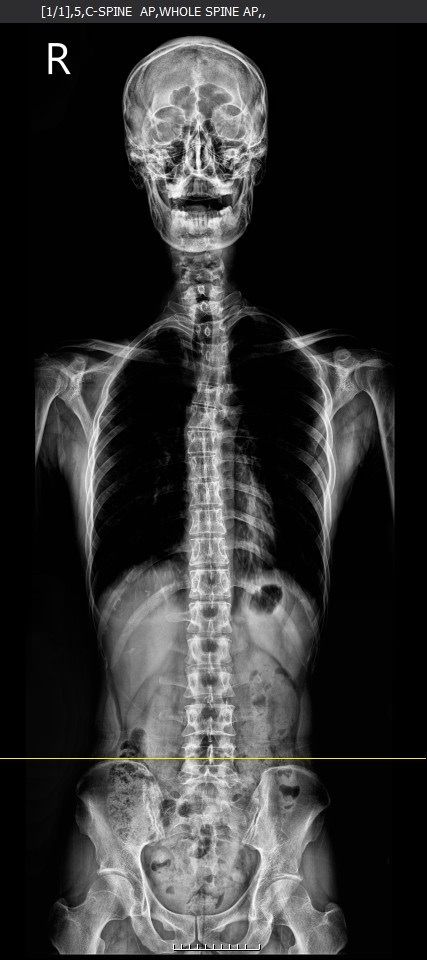

병원에서 일자목이면 경추성 어지럼증도 의심을 해보라고 하더라구요. 그래서 정형외과를 가서 엑스레이를 일단 찍어봤는데 전체적인 척추정렬이 삐둘어져있고 상부경추가 일자목이라서 의심은 된다고 하나 확답은 못주시네요.

여러 전문가분들께서 사진을 보시고 그 확률이 얼마나 될지 많은 조언을 주시면 감사하겠습니다.

• 1번 째 사진